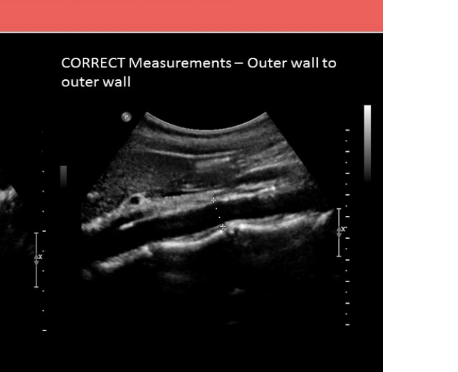

what is the proper caliper placement for assessing portal vein diameter

.

a) inner to inner wall at the junction of splenic vein + portal vein

b) outer to outer wall at the junction of splenic vein + portal vein

c) outer to outer wall where portal vein crosses IVC

d) inner to inner wall where portal vein crosses IVC

d. inner to inner wall where portal vein crosses IVC